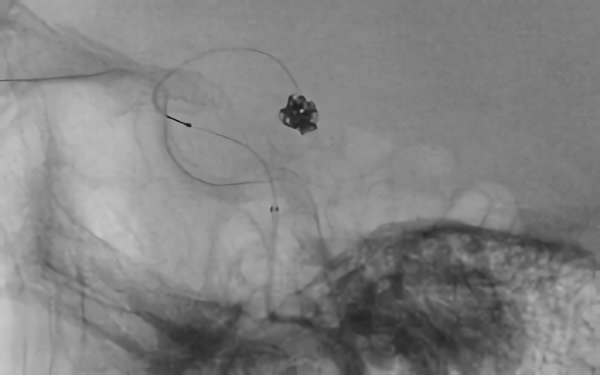

No.1631 手術前

No.1631 手術中

No.1631 手術後